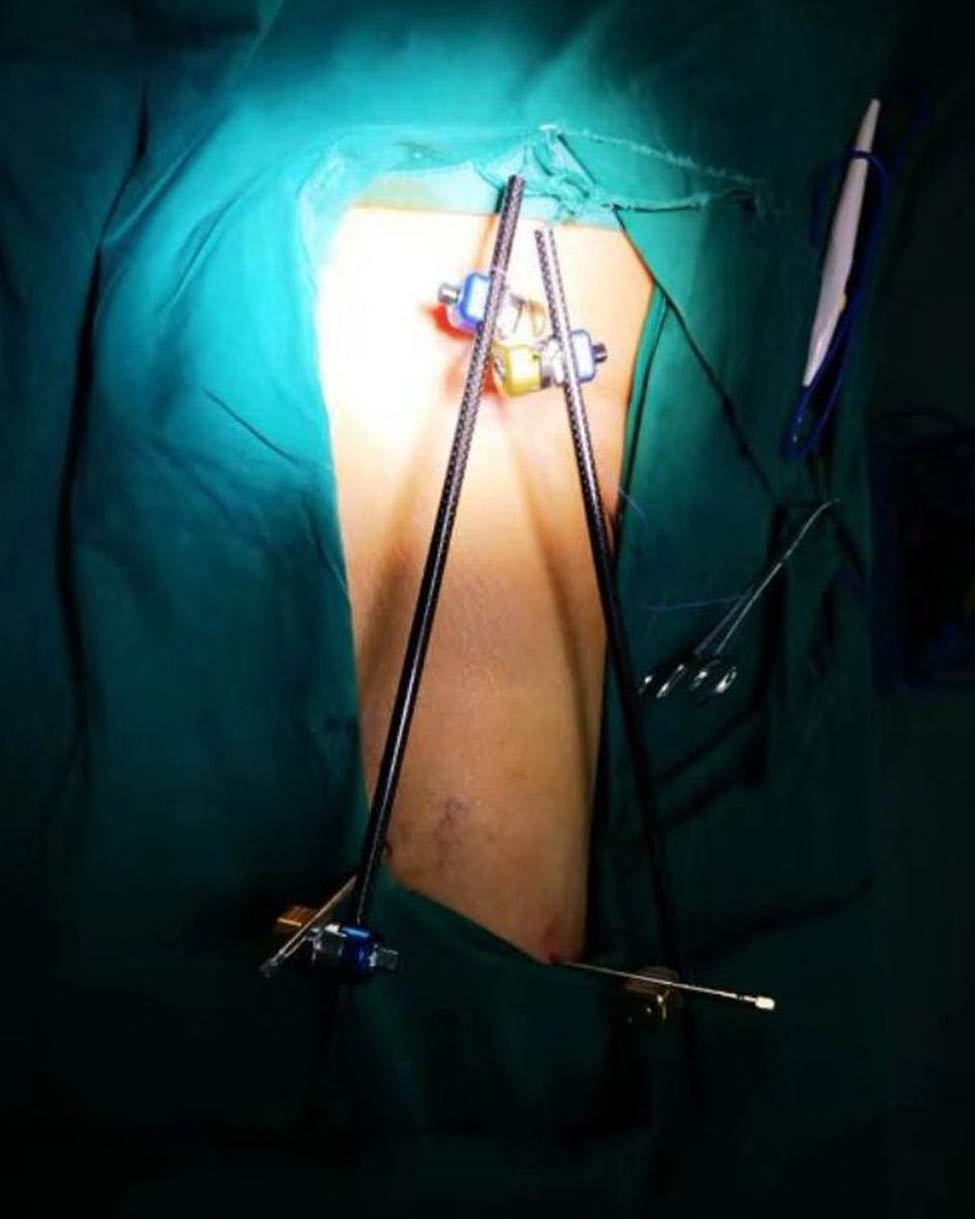

External fixation via the AIIS and distal femur was performed by a single surgeon under general anesthesia without regional nerve blockade during emergency surgery. External fixators derived from AO (Synthes, Ltd., Paoli, PA), Trauson (Trauson, Ltd., Changzhou), and Carefix (Carefix, Ltd., Shanghai) were used. Patients were placed in a supine position on the operating table. A C-arm was used to locate the points of the AIIS, and a minimal incision of 1–2 cm in length was made. The deep fascia of the pelvis and femur were incised. Proximally, the lateral femoral cutaneous nerve was protected by a surgical hook. One pin (diameter 6.0 mm, length 180 mm, thread length 60 mm) was placed at the AIIS on the same side as the PFF. Distally, two crossing pins (diameter 6.0 mm, length 180 mm, thread length 60 mm) were placed at the distal femur through two minimal incisions. High-strength and fully transparent carbon fiber rods (diameter 8 mm, length 400 mm) were fixed, manipulative reduction was performed along the strength line under the C-arm, and the clamps were tightened. The incisions were then sutured. A typical case is presented in Figures 2–5.

A patient with femoral intertrochanteric fracture was fitted with an external fixator during emergency surgery.